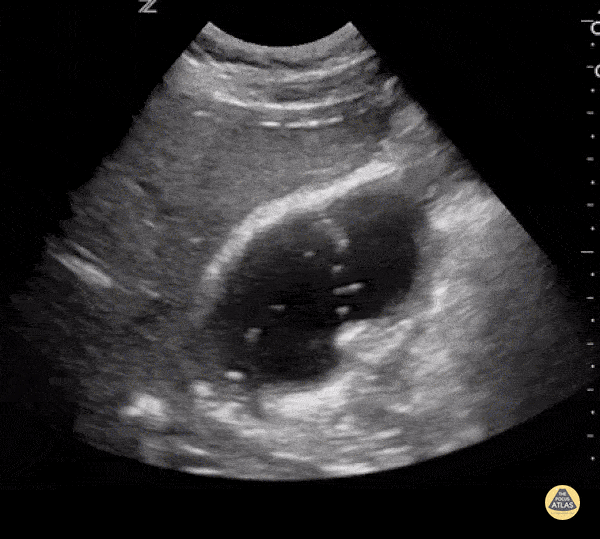

Bowel-GI - Duodeno-Biliary Fistula

Tiny bubbles of air float up to the top of the gallbladder. This finding prompted additional work-up and an ultimate diagnosis of duodeno-biliary fistula. Rachel Haney, MD - Massachusetts General Hospital